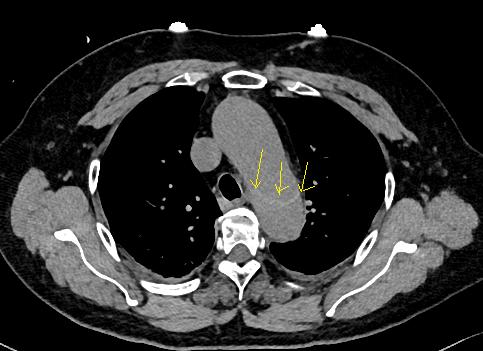

病例4

鲁迅说:孔乙己大约的确已经挂了!

下图的胸部CT平扫,基本上大约肯定可以看到一条线样阴影,将主动脉一分为二!

图10

增强CT一看,主动脉裂开了!

图11